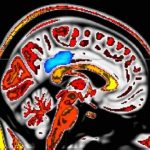

Study: Pain response in babies’ brains controlled in ‘similar way to adults’ — ...

Researchers from the Department of Paediatrics and Wellcome Centre for Integrative Neuroimaging at the University of Oxford, UK, have identified the neural network...